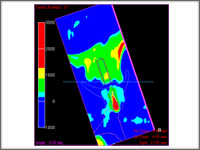

研究用模型の合成

インプラント断面において、 ハンスフィールドユニット(CT値)をカラーリング表示できます。インプラント断面を回転させながら、安全かつ骨密度の高い位置への埋入シミュレーションができます。 インプラント断面において、 ハンスフィールドユニット(CT値)をカラーリング表示できます。インプラント断面を回転させながら、安全かつ骨密度の高い位置への埋入シミュレーションができます。